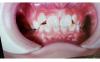

У дочки выпали три зуба снизу молочных,лезут коренные им места не хватает,сверху все молочные еще.

Одна врач сказала надо срочно расширять челюсть сверху и снизу,другая сказала надо ждать пока снизу вылезут все 4 коренных,нет смысла ставить расширитель пока они не вылезли.Сверху можно тоже не сейчас,подождать пока коренные полезут.